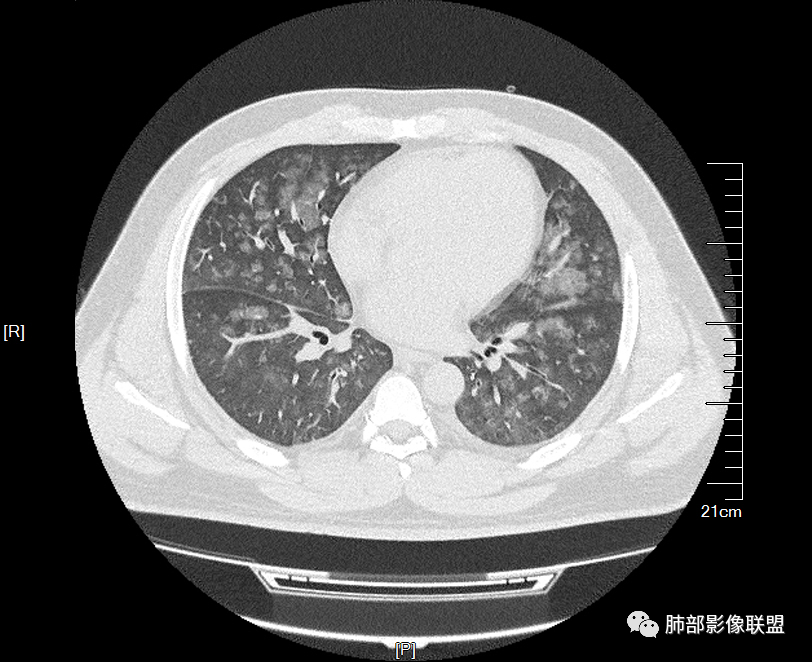

双肺多发腺泡结节及磨玻璃,小叶间隔增厚(大网格状),腺泡结节内及磨玻璃内可见细网格影(小叶内间隔增厚),影像表现符合肺泡出血改变,血肌酐升高,考虑肺肾综合征。鉴别肺水肿。

两肺弥漫向心分布的腺泡结节,部分融合,两肺小叶间隔增厚,血肌肝高,考虑肺泡性肺水肿

青年男性,痛风、肾功能不全病史,双肺多发结节状、斑片状阴影,支气管血管束增粗,可见支气管袖口征,叶间裂及小叶间隔增厚,考虑肺水肿。

年轻男性,既往血肌酐升高,左足痛六天入院,有痛风及高血压病史。CT示双肺多发磨玻璃结节影,不规则,部分融合成团或片状,小叶间隔增厚,以双下肺为明显,叶间胸膜亦见增厚。考虑为1.Good-Pasture综合征。2.病毒性肺炎?3.肺水肿?

年轻男性,痛风史,高血压史,肌酐高,左足痛6天入院。胸CT:双肺多发弥漫性磨玻璃结节影,大小不一,部分融合,上中下肺都有,中内带多,胸膜下少。部分血管束略增粗,小叶内间隔、小叶间隔增厚,下肺明显,左室大。叶裂胸膜增厚。临床有痛风,左足痛6天,考虑:心衰、间质性肺水肿?弥漫性肺泡出血?鉴别:MPA,肺肾综合征,痛风结节等。

青年男性,有肾功能不全史和痛风史,这个影像分布有个典型的特点,全部是以中央间质周围的渗出性改变,这个改变主要就是两种可能,一种是肾功能不全导致的血管通透性增高导致的肾性肺水肿,一种是出血导致的DAH改变,具体是哪种,影像上不好简单的鉴别,需要结合更多临床资料综合分析。

多发GGO结节,边界清,以全小叶、小叶中心为主:

中轴间质增厚,小叶间隔增厚,小叶内间质增厚,部分重力作用,双侧对称,胸水,按理淋巴道回流受阻有

肺水肿类病变有

问题是腺泡结节如何解释?

一般吸入性病变,肺泡腔充填性病变